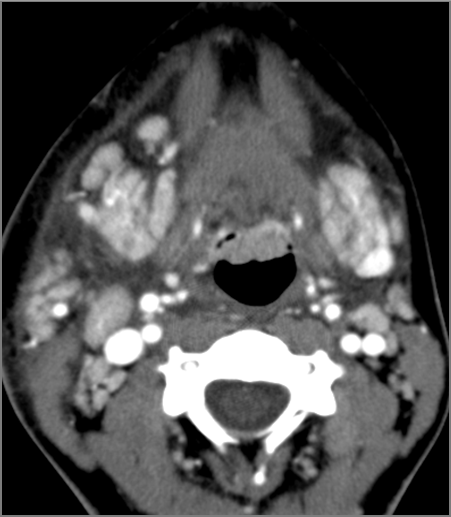

There is edema/abscess tonsillar or otherwise or likely suppurative retropharyngeal adenitis involving the oropharynx or adjacent deep tissue spaces. |

Yes | NA |

There is edema/abscess arising from the hypopharynx, larynx, thyroid gland or trachea. |